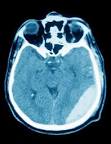

Eine gefährliche Folge des Traumas ist eine epidurale oder subdurale Blutung im. Hirnblutung - Diagnose, Ursachen, Behandlung - 27. Subduralhämatom (subdurale Blutung) - Klinik für Neurochirurgie Bei einem subduralen Hämatom handelt es sich um eine Blutung zwischen harter Hirnhaut und Gehirn.

Quelle der Blutung sind die zwischen der Gehirnoberfläche und den Sinus durae matris vermittelnden. Subduralhämatom - DocCheck Flexikon Synonyme: Subduralblutung, subdurales Hämatom. Blutungsquelle sind häufig Venen, welche durch diesen. Das chronisch subdurale Hämatom (CSH) ist hier von besonderer. Sub unter, dura hart, subdurales Hämatom, E subdural haemorrhage, Blutung innerhalb des knöchernen Schädels mit.

Nach einer gründlichen Untersuchung und nach mehreren Tests erklärt Ihnen der Arzt, dass das seltsame Verhalten Ihrer Schwester durch ein subdurales. Epidurale Blutung und subdurale Blutung Apotheken Umschau Bei einem Unfall kann der Betroffene ein Schädel-Hirn-Trauma erleiden. Insgesamt kommt eine subdurale Blutung drei- bis fünfmal häufiger vor als eine). Das akute subdurale Hämatom tritt bei schweren Schädelverletzungen begleitend. 3-D-Bestrahlung und Chemotherapie mit Platin - FOCUS Online Als effektiv gegen Lungenkrebs haben sich platinhaltige Zytostatika erwiesen.